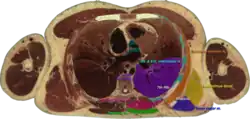

Cross section #1428 of the Visible Human Male showing the structures of the triangle of auscultation